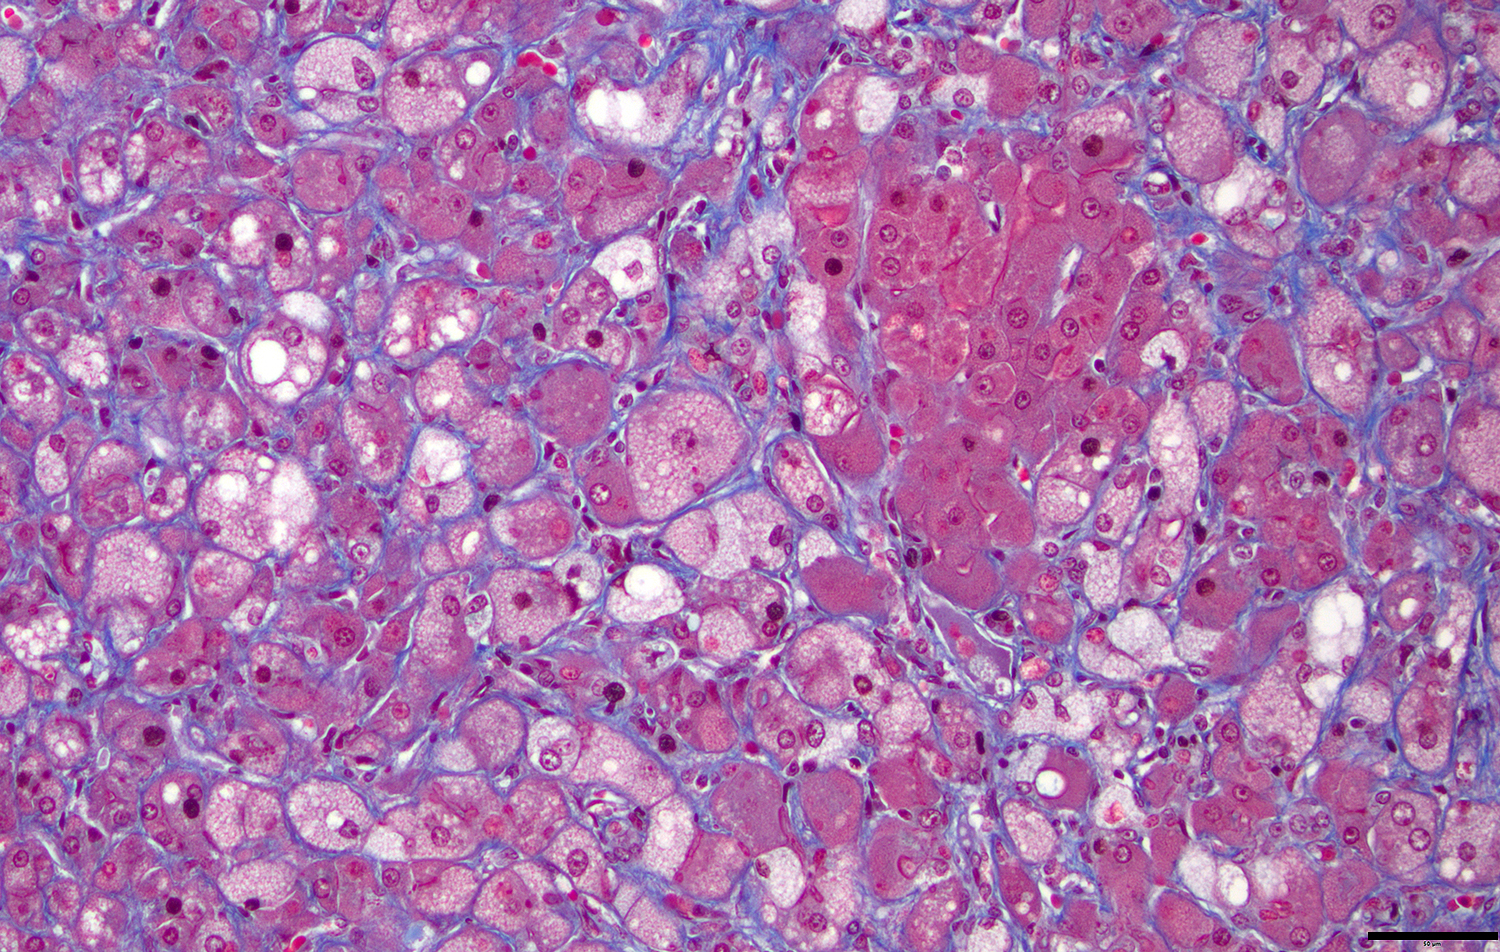

Microscopic Description: Approximately 60% of the hepatocytes in mostly periportal and centrilobular regions are markedly expanded by high numbers of microvesicular vacuolations (steatosis/lipid) and more rarely macrovesicular vacuolations or a mixture of the two. Sinusoids contain increased myofibroblasts (activated hepatic stellate cells) causing multifocal collapse of hepatocellular cord architecture. The myofibroblasts extend near portal areas, but distinct biliary hyperplasia is not appreciated. Occasionally hepatocytes are dissociated and composed of hypereosinophilic cytoplasm and lack a nucleus (necrosis). There are occasional binucleated hepatocytes. Canaliculi are multifocally, mildly expanded by tan to brown material (bile). Very rare lymphocytes are within sinusoids and in portal areas.

The liver histopathology in this case also provided opportunity to review the classic lesions of liver repair. One group of progenitor cells in the liver (also termed oval cells in rodents) is located within the canals of Hering. When the liver is damaged, these cells are activated and lead to histopathologic “biliary duct hyperplasia”, “ductular reaction”, or “oval cell activation” 8. In addition to this population of progenitor cells are hepatic stellate cells. Hepatic stellate cells reside in the space of Disse along the sinusoids and are activated from relatively quiescent cells into myofibroblasts when there is liver damage3,8. This case highlights early fibrosis within the sinusoids or space of Disse due to activation of hepatic stellate cells.

JPC Diagnoses: Liver: Hepatocellular micro- and macrovesicular lipidosis, chronic, multifocal to coalescing, severe, with marked stellate cell hyperplasia and cholestasis.

The contributor in this case provided a well-thought and informative writeup of hepatic lipidosis and hyperlipidemia, and much of what was discussed in conference is covered in their comment. Conference participants were, for the most part, readily able to achieve the reach the correct morphologic diagnosis in this case, but there was some speculation on the origin of the hyperplastic spindle cell population on the H&E. As mentioned by the contributor, there are two main possibilities: oval cells or stellate cells. Oval cells are bipotential progenitors of both hepatocytes and biliary ductular epithelial cells. Hepatic stellate cells, also called Ito cells, live primarily in the space of Disse, store Vitamin A, and can be activated into myofibroblasts following injury that will produce connective tissue components.3,8 Participants wondered if there was both oval cell and stellate cell hyperplasia in this case due to the presence of mild ductular reaction, cholestasis, and fibrosis, but unanimously agreed that there was at least stellate cell activation due to the fibrosis highlighted by a Masson’s trichrome. This is a difficult distinction to make on H&E alone.